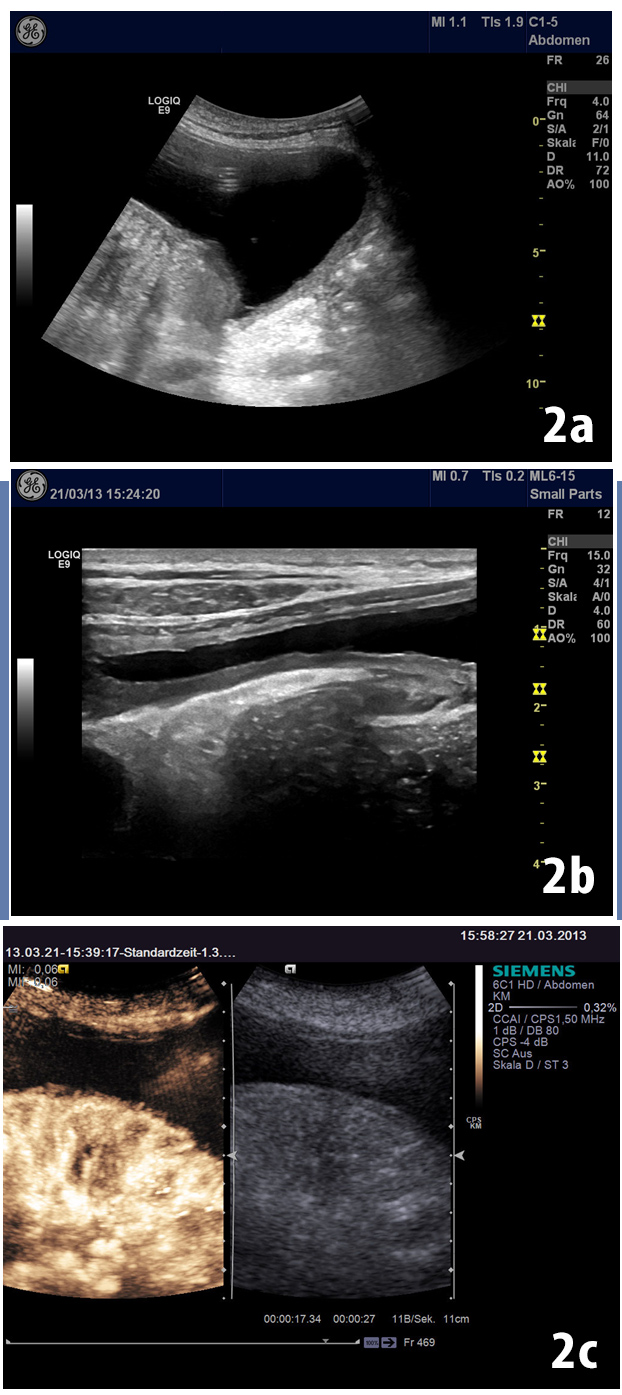

A large cystic lesion was detected on B-mode ultrasound with thick capsule wall (Fig 2).

Figure 2: A large cystic lesion was detected on B-mode ultrasound (a) with thick capsule wall (b). Displacement of the bowel gas pattern and absence of shifting dull-ness could be noticed. Conventional contrast enhanced ultrasound revealed the characteristic enhancement pattern (c).